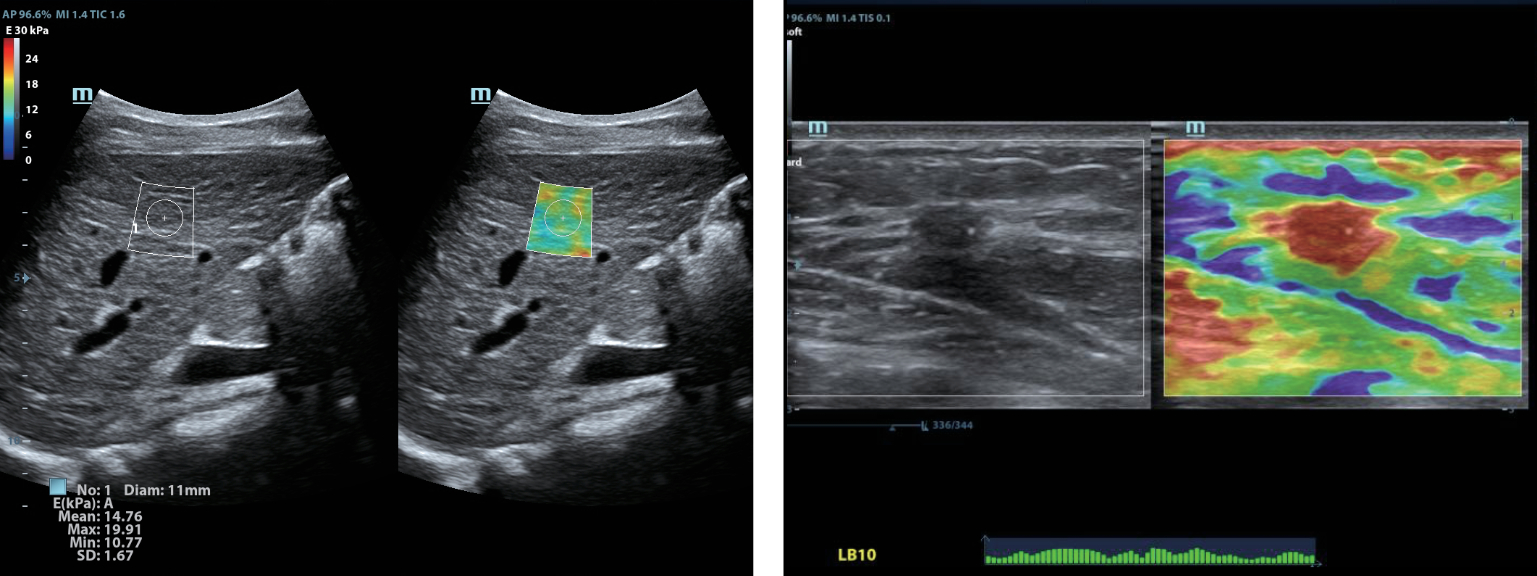

–€–Ψ–Ϋ–Ψ–Κ―Ä–Η―¹―²–Α–Μ–Μ–Η―΅–Β―¹–Κ–Η–Β –¥–Α―²―΅–Η–Κ–Η ―¹ ―²–Β―Ö–Ϋ–Ψ–Μ–Ψ–≥–Η–Β–Ι 3–Δ?

–ë–Μ–Α–≥–Ψ–¥–Α―Ä―è ―¹–Ψ―΅–Β―²–Α–Ϋ–Η―é ―²–Β―Ö–Ϋ–Ψ–Μ–Ψ–≥–Η–Η 3–Δ? (–Δ―Ä–Ψ–Ι–Ϋ–Ψ–Ι ―¹–Ψ–≥–Μ–Α―¹―É―é―â–Η–Ι ―¹–Μ–Ψ–Ι, ―²–Β―Ö–Ϋ–Ψ–Μ–Ψ–≥–Η―è –Ω–Ψ–Μ–Ϋ–Ψ―¹―²―¨―é ―Ä–Α–Ζ–¥–Β–Μ–Β–Ϋ–Ϋ―΄―Ö –Κ―Ä–Η―¹―²–Α–Μ–Μ–Ψ–≤, ―²–Β―Ä–Φ–Ψ–Κ–Ψ–Ϋ―²―Ä–Ψ–Μ―¨ –Α–Κ―É―¹―²–Η―΅–Β―¹–Κ–Ψ–Ι –Μ–Η–Ϋ–Ζ―΄) –Η –Φ–Ψ–Ϋ–Ψ–Κ―Ä–Η―¹―²–Α–Μ–Μ–Η―΅–Β―¹–Κ–Η―Ö –¥–Α―²―΅–Η–Κ–Ψ–≤ –Ψ–±–Β―¹–Ω–Β―΅–Η–≤–Α–Β―²―¹―è –Κ–Α–Κ –±–Ψ–Μ–Β–Β –≤―΄―¹–Ψ–Κ–Α―è ―Ä–Α–Ζ―Ä–Β―à–Α―é―â–Α―è, ―²–Α–Κ –Η –Ω―Ä–Ψ–Ϋ–Η–Κ–Α―é―â–Α―è ―¹–Ω–Ψ―¹–Ψ–±–Ϋ–Ψ―¹―²―¨, –≤ ―Ä–Β–Ζ―É–Μ―¨―²–Α―²–Β ―΅–Β–≥–Ψ ―Ä–Β―à–Α–Β―²―¹―è –Ω―Ä–Ψ–±–Μ–Β–Φ–Α –Η―¹―¹–Μ–Β–¥–Ψ–≤–Α–Ϋ–Η–Ι ―²–Β―Ö–Ϋ–Η―΅–Β―¹–Κ–Η ―¹–Μ–Ψ–Ε–Ϋ―΄―Ö –Ω–Α―Ü–Η–Β–Ϋ―²–Ψ–≤.